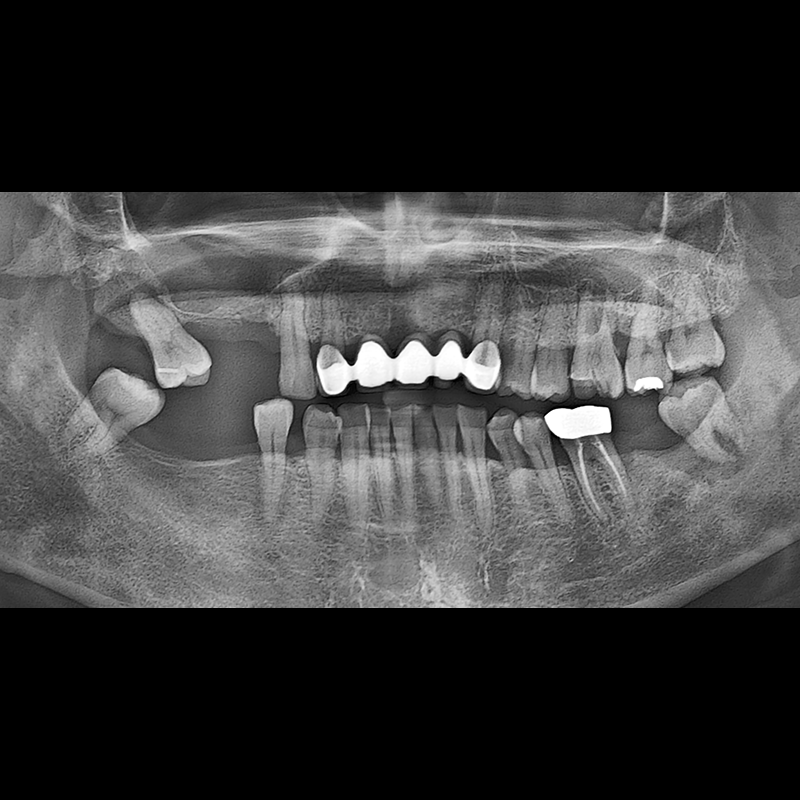

BEFORE AFTER

种植牙前后的照片 2025.05.30

在缺失的牙齿部分和难以挽救的牙齿位置植入了种植牙。